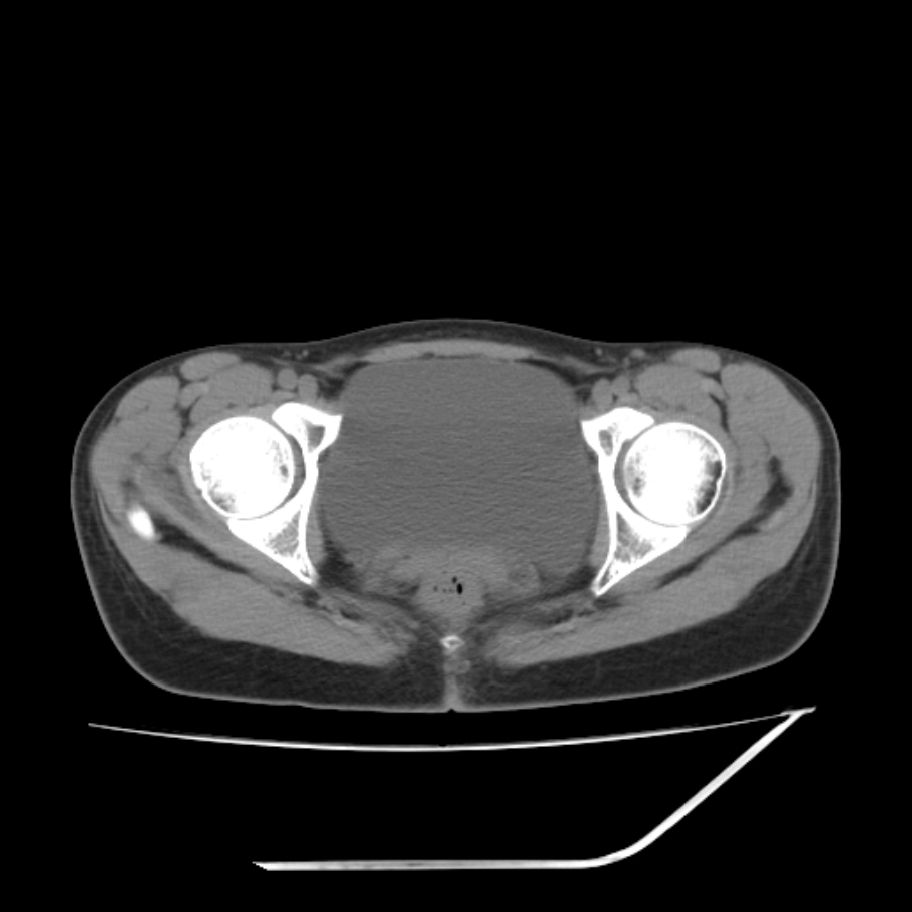

女,25岁。偶尔有右下腹不适感,余无明显异常。(结婚半年),囊壁较厚,是卵巢囊肿吗?

其上一层面见两枚小气泡影,考虑为肠管影可能,不完全除外囊肿

右侧卵巢区椭圆形囊性肿物,内壁光滑 无分隔。直肠子宫间隙内有少量积液征象。结合临床考虑卵巢巧克力囊肿,还要问问有没有痛经,本例ct怎么没有灌肠?要是灌肠或前一前口服造影剂,起码可以和肠管区别开

b超示:囊实性占位,畸胎瘤?临床有痛经。

考虑右侧卵巢囊性占位性病变(巧克力囊肿?),盆腔积液有不排除宫外孕可能,请结合临床和b超。

右侧卵巢囊伴盆腔少量积液。